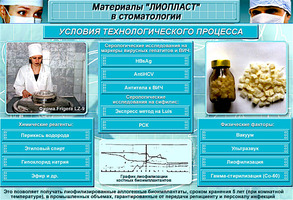

Способ консервации-лиофилизация.Способ стерилизации-гамма лучи.

1. Очистка и обработка материала. Получение биоиплантата "Лиопласт"

5. Анализы и свойства биоимплантатов "Лиопласт"